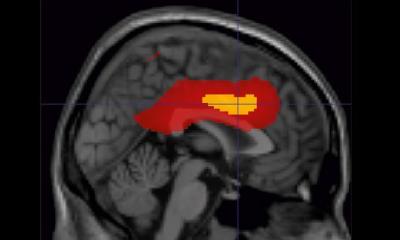

Die Amyotrophe Lateralsklerose (ALS) ist eine unheilbare, schwere Erkrankung des Nervensystems. In ihrem Verlauf sammeln sich fehlgefaltete Eiweiße in den für die Muskelbewegung zuständigen motorischen Nervenzellen in Gehirn und Rückenmark, verursachen Entzündungen und schädigen diese Motoneuronen genannten Zellen nachhaltig.

Um zu schauen, was passiert, wenn der MIF-Spiegel wieder hochgefahren wird, kurbelten die Forschenden mit Hilfe einer virus-vermittelten Genfähre die Produktion von MIF in den Nervenzellen wieder an. Die so ausgelöste Steigerung der MIF-Produktion sorgte in den menschlichen Nervenzellen dafür, dass sich weniger fehlgefaltetes SOD1-Protein ablagerte. Und auch im Tiermodell funktioniert der Wirkmechanismus: Die virusvermittelte Einschleusung von MIF in das zentrale Nervensystem des SOD1-Mausmodells führte zur Verbesserung der Muskelfunktionen, es häufte sich weniger fehlgefaltetes SOD1-Protein an, Entzündungsreaktionen im Rückenmark gingen zurück, der Krankheitsverlauf verlangsamte sich und die Tiere überlebten länger. „Unsere Untersuchungen zeigen somit eine spannende neue Therapieoption der unheilbaren neurodegenerativen Erkrankung ALS auf“, betont Professorin Petri. Nun müssten klinische Studien folgen, die zeigen, ob diese Methode nur in Zellkultur und Tiermodell funktioniert, oder irgendwann auch für die Behandlung von ALS-Patienten erfolgreich eingesetzt werden kann.